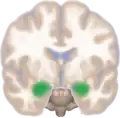

Dorsal view of the amygdalae in an average human brain

Frontal view of the amygdalae in an average human brain